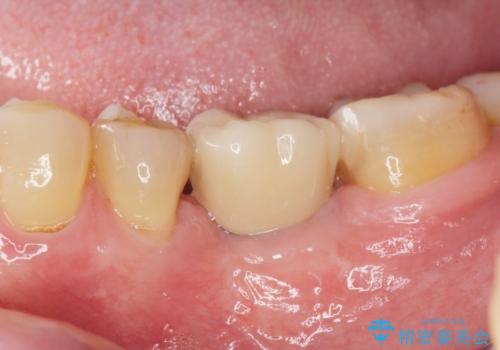

インプラントを適切な位置に埋入することで、清掃性が高くしっかりと咬合力に耐えられるようなインプラント治療を行うことができます。